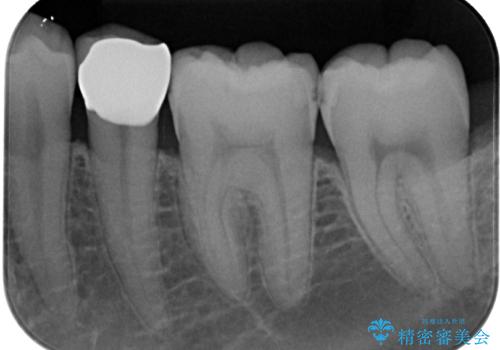

- 左下の奥歯のところがフロスが引っかかったり、ちぎれたりするとのことで来院された患者様です。検査の結果、神経は正常な反応を示し、フロスは引っかかる状態でしたので、虫歯治療も併せて行うためにオールセラミッククラウンによる補綴治療を行っていくことにしました。

拡大鏡視野下でプラスチックの詰め物、虫歯を除去しオールセラミッククラウンに適した形に整えました。

歯と歯茎の間に圧排糸と言われる糸を入れてシリコーン印象材にて型どりをしました。

フロスがちぎれることもなくなり、被せものが入っていることを忘れていたと大変喜んでいただきました。適合の良い被せものは二次的な虫歯の再発リスクを低減してくれます。